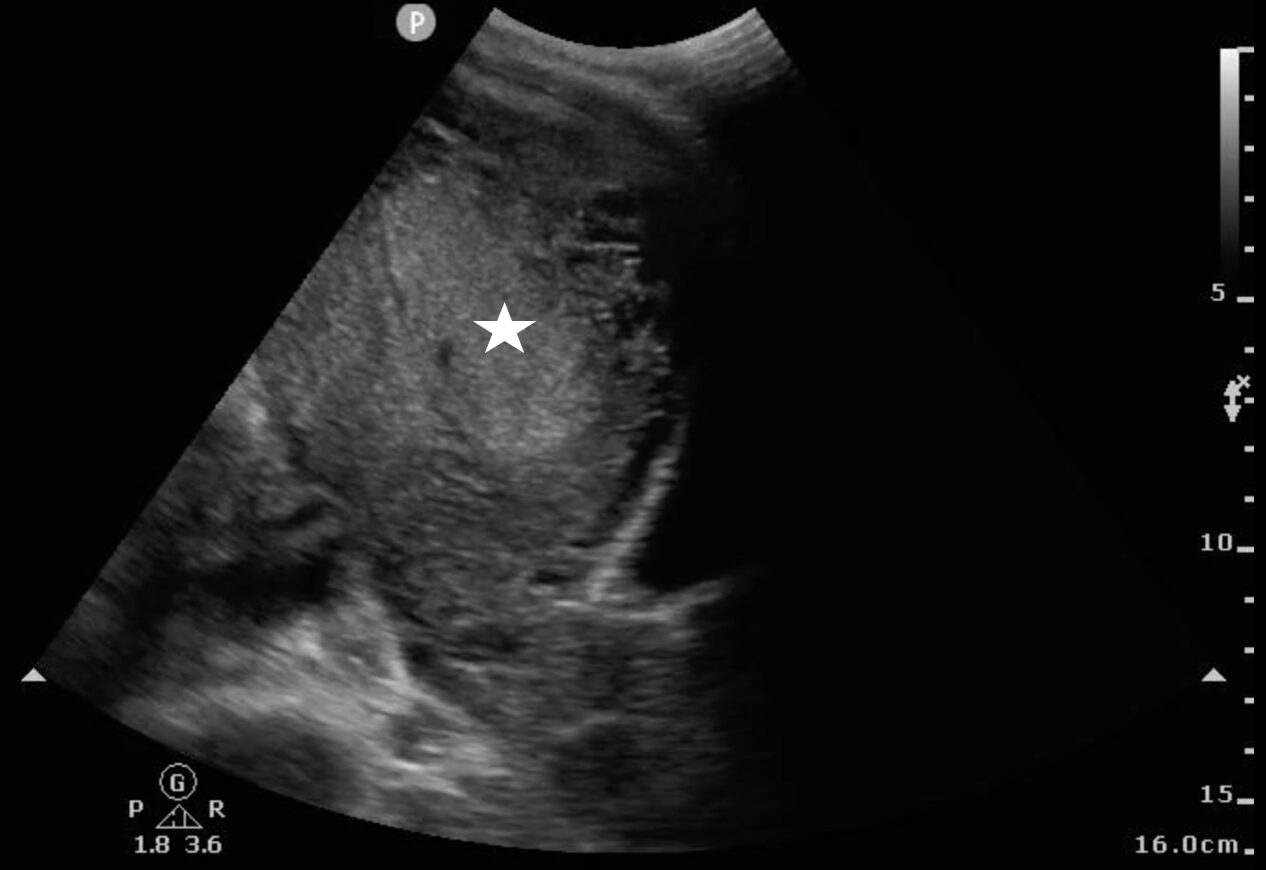

Endometrial thickness measurements using ultrasound have been shown to be more reliable for diagnosis RPOC than history alone.1-4 RPOC often appears with a heterogeneously thickened endometrium > 10 mm, but other studies cite > 15 mm for the diagnosis.5 Ideal visualization of RPOC occurs through transvaginal POCUS (Image 3) (Video 2), but transabdominal POCUS can also be accurate in diagnosing RPOC (Image 4) (Video 3). To date, only one study has evaluated for RPOC using POCUS, which demonstrated 93.8% specificity and 79.0% sensitivity for identifying RPOC.6

Image 4: Transabdominal ultrasound showing a thickened endometrial stripe (white star)

suggestive of retained products of conception